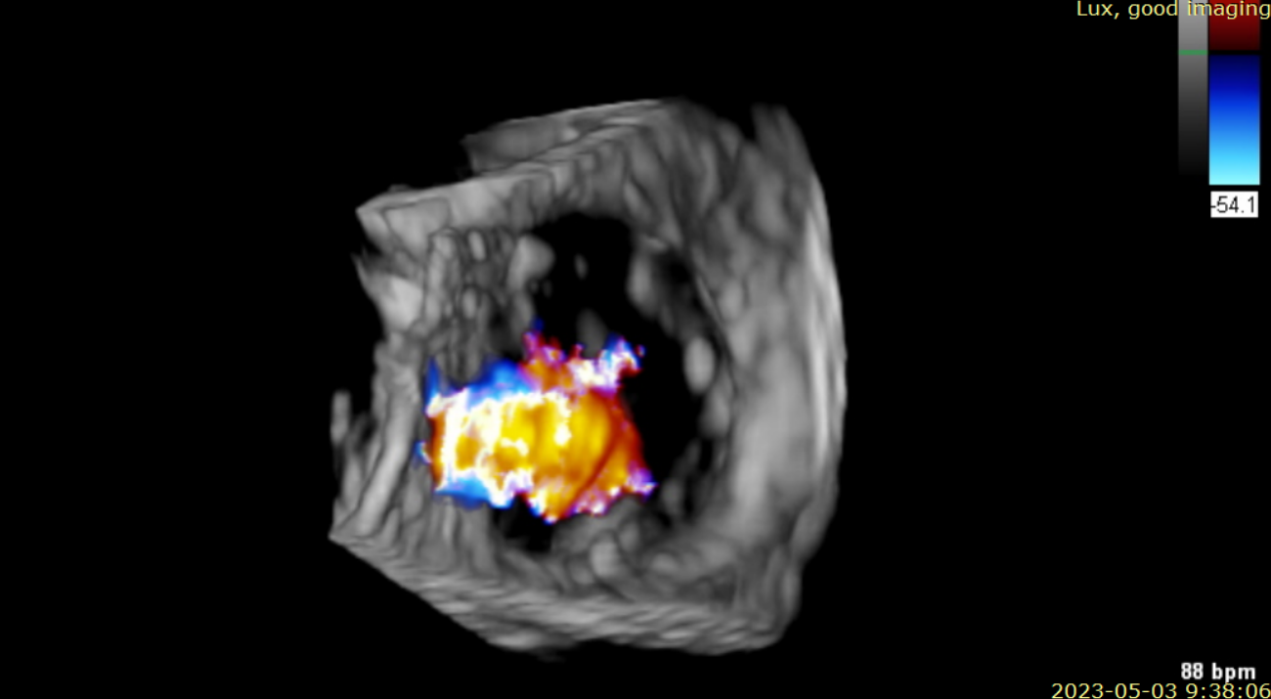

術前超聲提示大量三尖瓣反流

術中輸送器在超聲引導下調整位置

術后超聲提示無瓣周漏